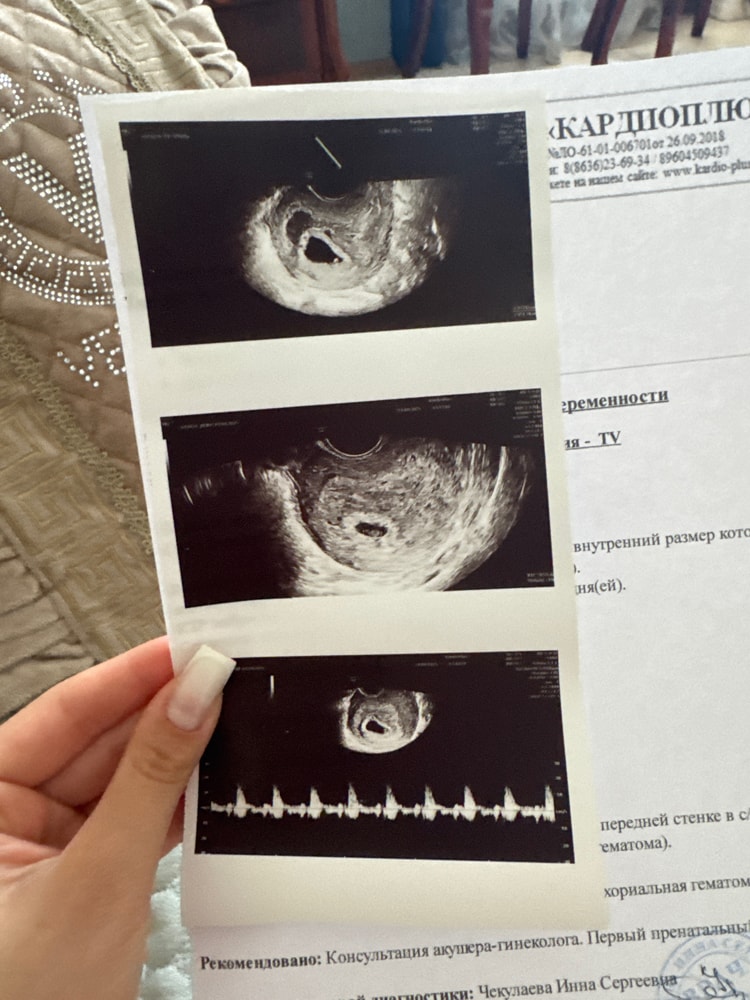

Ретрохориальная гематома 7 недель беременности

сегодня впервые у слышала сердце малыша ,но радовалась не долго,врач быстро выключила сердцебиение и сказала , чтобы я не ныла (дословно) у нее в кабинете . Посмотрела малыша и в конце сказала , рано радуешься , у тебя гематома…